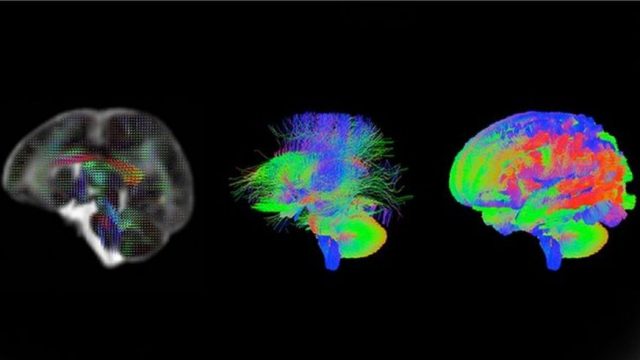

Su nivel de detalle no tiene precedentes: muestra cómo viaja la información en el cerebro y cómo se hacen más denso o fino su «cableado».

La innovadora tecnología para escanear el cerebro y ver sus conexiones internas fue desarrollada por científicos de la Universidad de Cardiff, en Reino Unido, y permite ver las fibras que transportan todos los procesos de pensamiento.

Fergus Welsh, especialista en salud de la BBC, se sometió al escáner y las imágenes de este video son de su propio cerebro.

Lo extraordinario, explica Welsh, es la capacidad de este escáner de variar su campo magnético rápidamente de acuerdo a la posición.

Esto supone que los investigadores pueden hacer un mapa de las conexiones –llamadas axones-con tal nivel de detalle que harían falta 50 de estas fibras para alcanzar el grosor de un cabello humano.